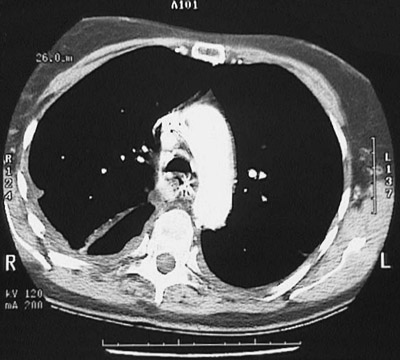

This chest CT scan taken with "soft tissue" window reveals an

empyema

.